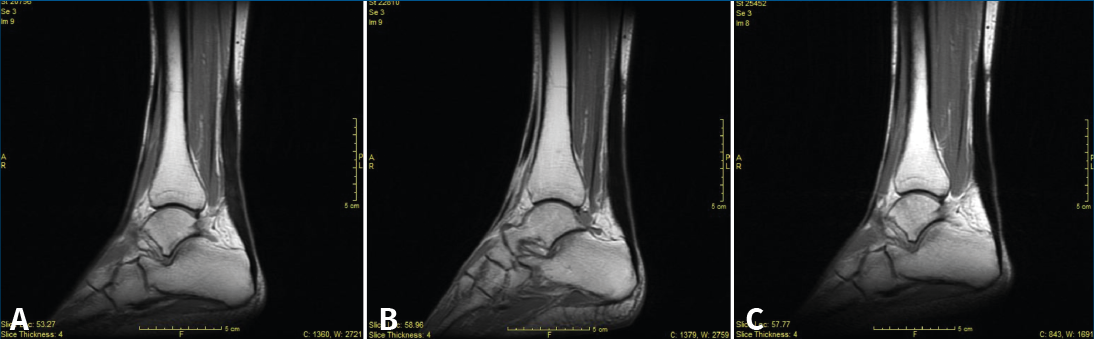

Figura 3. Secciones sagitales de resonancia magnética de SE T1, a los 3 (A), 6 (B) y 12 meses (C).

A los 3, 6 y 12 meses se recogió el balance articular del tobillo, el diámetro de la pantorrilla, la altura del talón al suelo bipodal y el grosor del tendón. Se pasaron los cuestionarios AOFAS, SF-36 y ATRS, y también se realizaron RM (Figura 3) y ecografía. A los 12 meses se practicó una exploración dinamométrica isocinética.

Los hallazgos en las RM y las ecografías de control se encuentran recogidos en las Tablas 1 y 2. En la Figura 3 podemos observar el característico engrosamiento tendinoso durante la evolución postoperatoria. Las complicaciones postoperatorias quedan recogidas en la Tabla 3.

Karjalainen et al. en 1997 publican un trabajo en el que realizan RM a 21 pacientes postoperados de roturas del tendón de Aquiles y observan que existe una correlación entre la mala evolución clínica y la existencia de lesiones intratendinosas con señal de alta intensidad(23). Igual que en el estudio de Karjalainen et al., en nuestro estudio se midió el área mayor del tendón y se comparó con el tendón contralateral, además de valorar cualitativamente las imágenes de RM(23). Los hallazgos más frecuentes mediante RM en ambos grupos de tratamiento fueron el engrosamiento, la heterogeneidad y el líquido peritendinoso. En 4 pacientes se encontró hiperseñal intratendinosa, que según Karjalainen et al. (1996) podría corresponder a formación de cicatriz fibrosa en el interior. Ellos encontraron este tipo de lesión en 4 de los 13 pacientes estudiados y, de ellos, los 2 con las lesiones más grandes fueron los que tuvieron una peor evolución clínica(24). En nuestro estudio, sin embargo, los 4 pacientes presentaban una correcta evolución.

Globalmente, en nuestro trabajo, los resultados tanto de la RM como de la ecografía mostraron cambios heterogéneos y engrosamiento en la mayoría de los pacientes como hallazgos más frecuentes. Este dato no mostró una significación clínica. En cambio, sí que pareció existir una relación entre el adelgazamiento tendinoso y la mala puntuación de los cuestionarios funcionales. Estos resultados sugieren que el adelgazamiento es un factor de riesgo o un indicador precoz de una posible rerrotura o de una mala evolución funcional.

En nuestro estudio morfológico mediante las técnicas de imagen utilizadas (RM y ecografía) no se han encontrado diferencias significativas entre ambos tratamientos. Los hallazgos más frecuentes son engrosamiento y heterogeneidad. El adelgazamiento se correlaciona con malas puntuaciones en los cuestionarios y rerroturas.